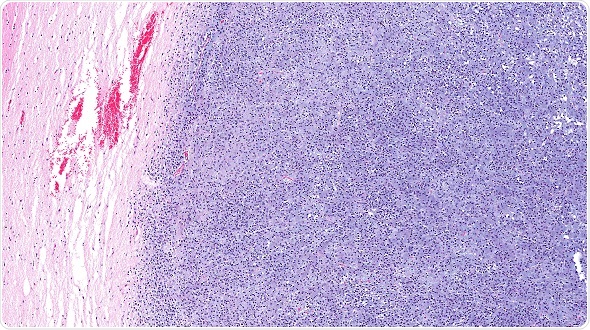

Image

Microscopic view of oligodendroglioma of the brain (right half blue) and normal brain (pink portion on the left). The brain cancer has invaded and replaced normal healthy brain tissue. Glioma of the brain. © vetpathologist / Shutterstock.com

In contrast, it is easy to differentiate between tumor tissue and non-cancerous tissue at the microscopic level. However, traditional histopathologic techniques involve tissue being removed from the operative field and sent  off for processing and staining, meaning these methods cannot be performed in situ or in real-time. An in vivo technique for identifying resection margins during surgical procedures would therefore be highly desirable.